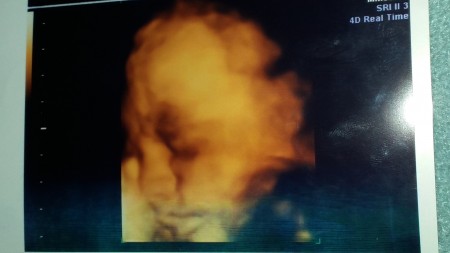

Radistanbul Goruntuleme Istanbul 0 216 5218836 4 Boyutlu Renkli Ultrason 0 216 5218836 Radistanbul Goruntuleme Merkezi 4d Us Ultrason Us Teknolojisindeki Gelismeler Daha Once Iki Boyutlu Olarak Izlenen Yapilarin Uc Boyutlu Olarak Incelenmesini